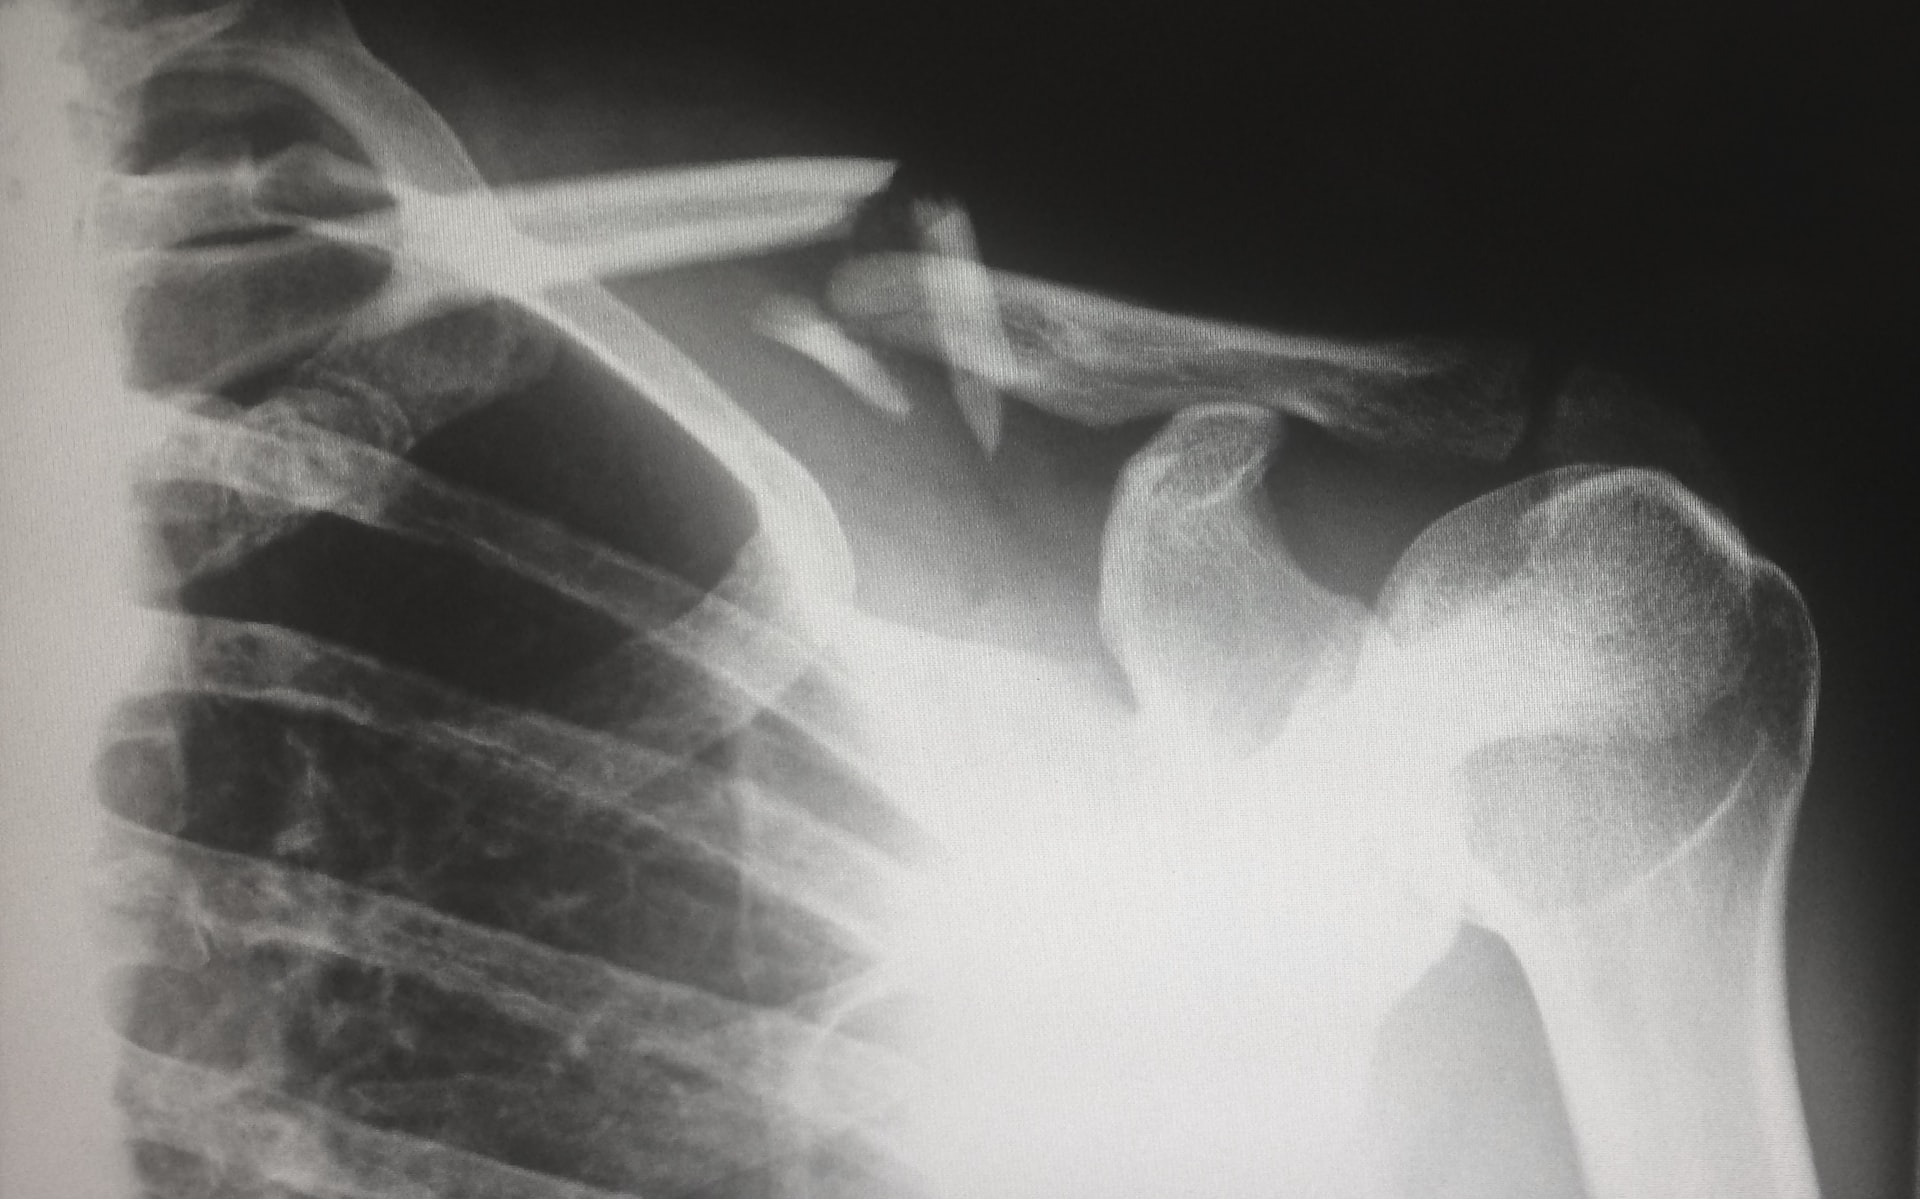

Если упали: жителям Самарской области назвали адреса травмпунктов

Если все же травмы избежать не удалось, вот адреса травмпунктов.